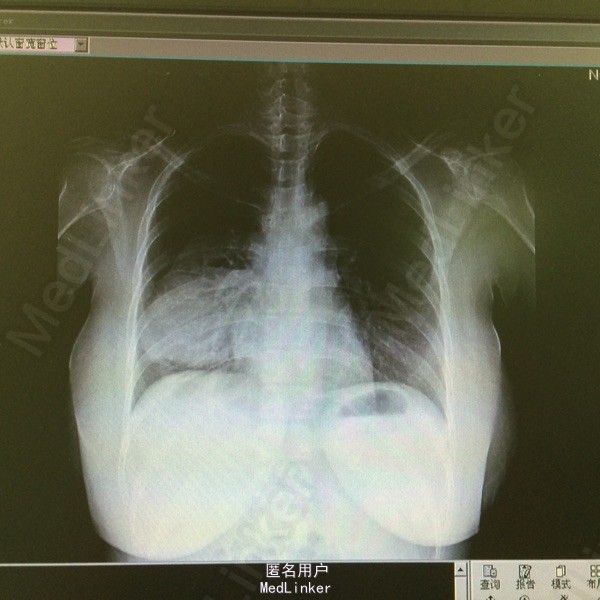

查体:轻度贫血貌,右下肺呼吸音减弱,双肺未及干湿罗音。腹部孕23+周状态。 辅助检查:胸片示:右中下肺野高密度影。血常规:HB 88g/l,白细胞、PCT、ESR、CRP均正常。